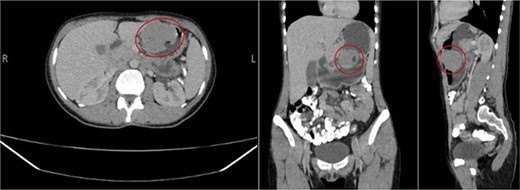

Consequently, initial laboratory tests were conducted and returned normal results. However, an ultrasound revealed a 5 × 6 cm cystic lesion. Therefore, further investigation through an abdominal CT scan with oral and intravenous contrast was warranted, which identified an oval-shaped lesion in the gastric lesser curvature (see Fig. 1), raising suspicion for a GIST. To further evaluate, an upper endoscopy and endoscopic ultrasound-guided fine needle biopsy (EUS-FNB) were performed, revealing a gastric mass extending from the lesser curvature to the greater curvature anterior wall. As a result, a central gastrectomy with clear surgical margins was performed, yielding a well-defined, elastic mass measuring 6 × 6 cm. Notably, the resected specimen exhibited no necrosis, lymph node enlargement, or additional lesions. Additionally, a follow-up abdominal CT scan confirmed the absence of metastasis.

Well-defined enhancing oval-shaped gastric lesion seen in the gastric lesser curvature with intra and extra luminal components; it presents a small ulcer at the intraluminal component.